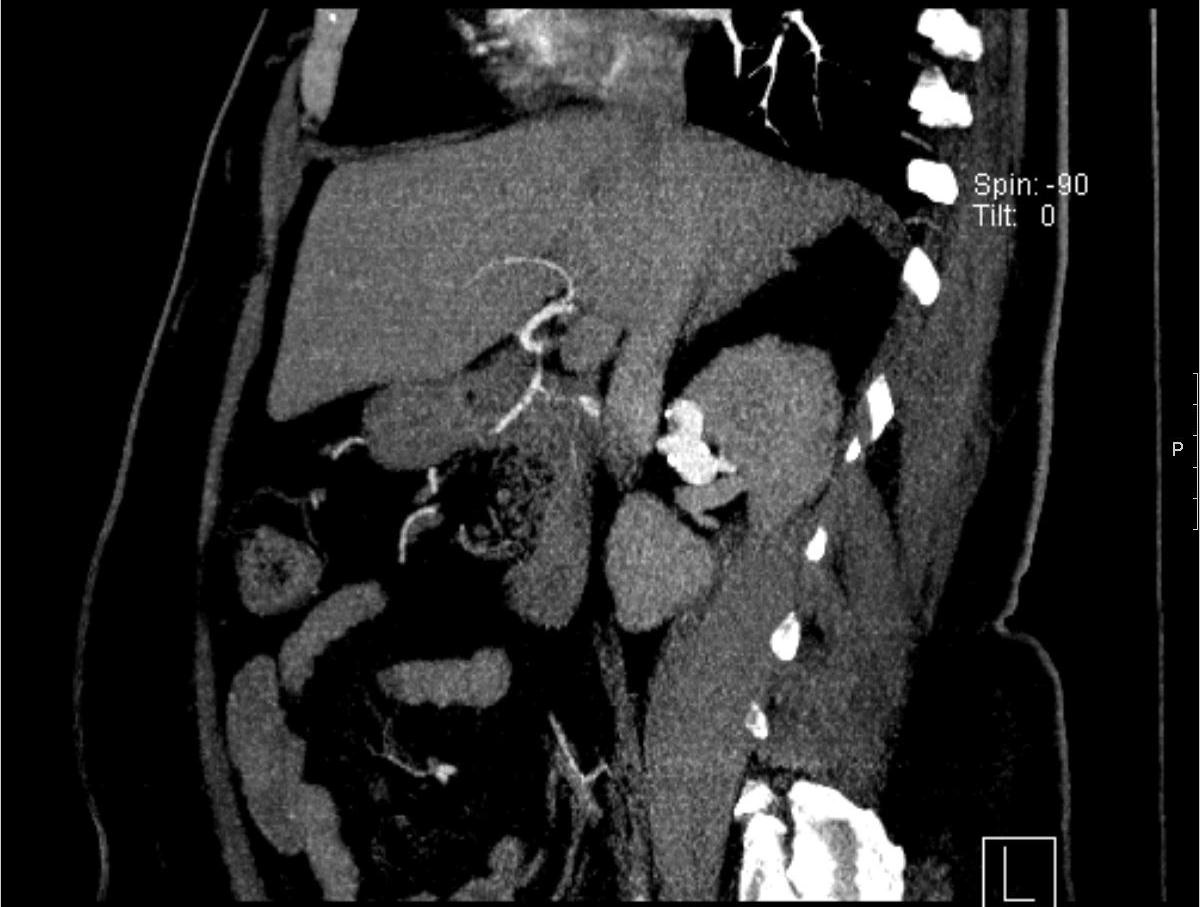

彩色多普勒超声:可以提供有效和非侵入性方式诊断肾动脉瘤。采用肾冠状切面主肾动脉全程扫查法,不受肠气干扰,而且声束血流夹角小,使肾动脉血流自腹主动脉起始端至肾门部均被完整显示。肾动脉瘤的特征性多普勒超声表现为局限性扩张膨出的肾动脉内显示红蓝相对的旋转式血流,即瘤腔内一侧为高速前向血流,对侧为低速逆向血流,该特征随瘤体增大而明显。瘤体内可合并血栓形成,血栓易附着于逆向低速血流一侧壁上。瘤口分入、出二个口,为收缩期单向前向血流。 CTA:用于肾动脉瘤诊断和随访的最为广泛的和可重复的影像诊断方法。解剖分辨率优于超声。3D重建技术可以精确地制定治疗计划。由于应用含碘造影剂所以有生命危险的碘过敏和肾功能不全的病人使用时应该慎重考虑。轻度过敏可以事先给抗过敏药物包括苯海拉明 (Benadryl) ,西咪替丁(cimetidine)和注射用甲强龙( Solu-Medrol)。

![]() 左肾囊性动脉瘤 ![]()

血管造影同一病人